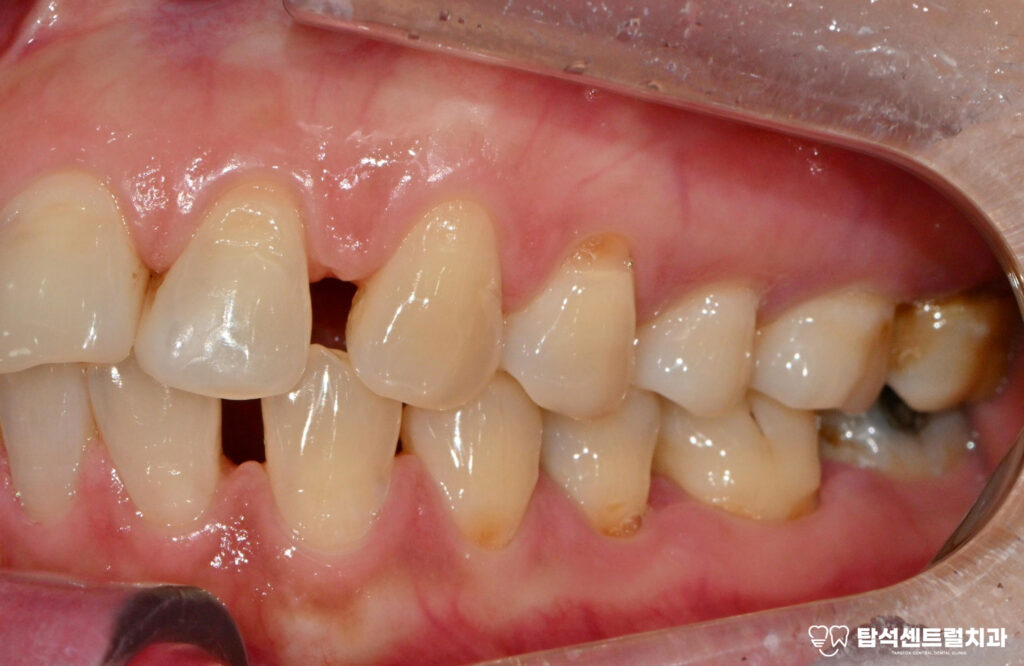

흔들리는 18번과 48번 사랑니 역시

발거가 필요한 상태였습니다.

사랑니는 안쪽에 위치해 있어

관리가 어렵고 염증을

유발하기 쉬운데요

다수 치아에서 나타난 치경부 마모증은

레진으로 수복하는 것이 적절합니다.

치경부 마모증은 치아 목 부분이 닳아서

움푹 파인 상태를 말하며,잘못된 칫솔질이나

이갈이 습관으로 발생합니다.